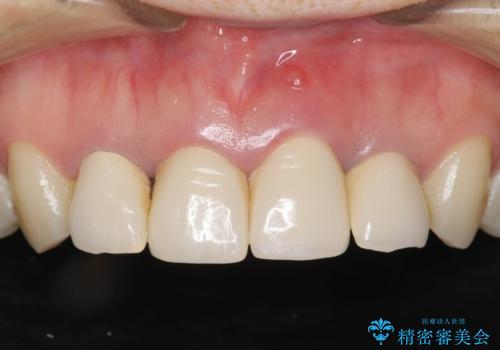

黒っぽい歯ぐきを改善したい メタルフリーセラミック治療

- 歯ぐきの黒っぽさ、暗い色調の前歯の改善を求めて来院されました。

金属のフレームを用いるクラウンは色調が暗くなる傾向にありますが、セラミッククラウンに置き換えたことで自然な明るさ、審美性を取り戻すことができました。